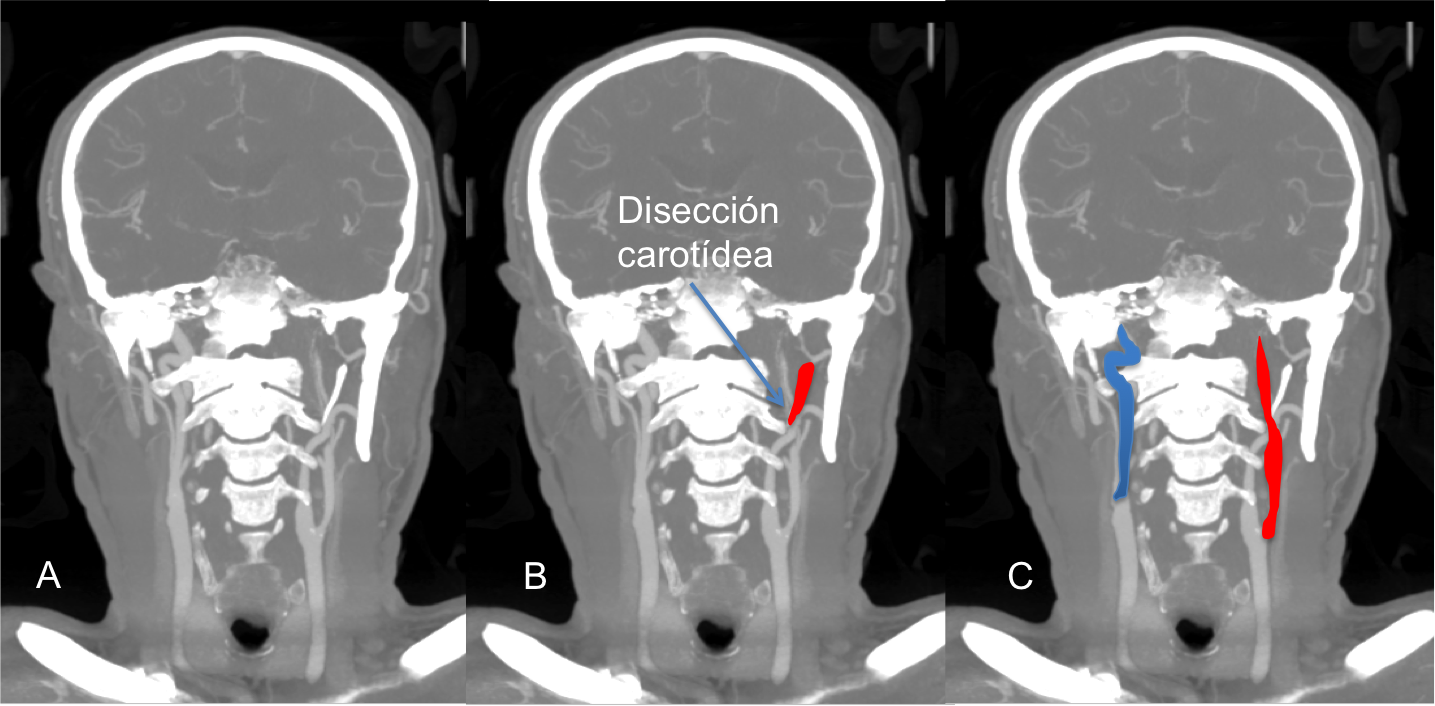

Os presento un paciente que debutó con una hemiplejía derecha y un afasia donde se observó a su llegada a urgencias en la TAC cerebral una lesión isquémica aguda en el territorio de la arteria cerebral media izquierda. En la AngioTAC de TSA se observa un cierre de la arteria carótida interna izquierda sugestivo de disección carotídea (figura 1. B flecha; en rojo porción distal de la apófisis estiloides). Posteriormente, se confirmó la presencia de hematoma intramural por resonancia cervical con secuencias T1 y T2.